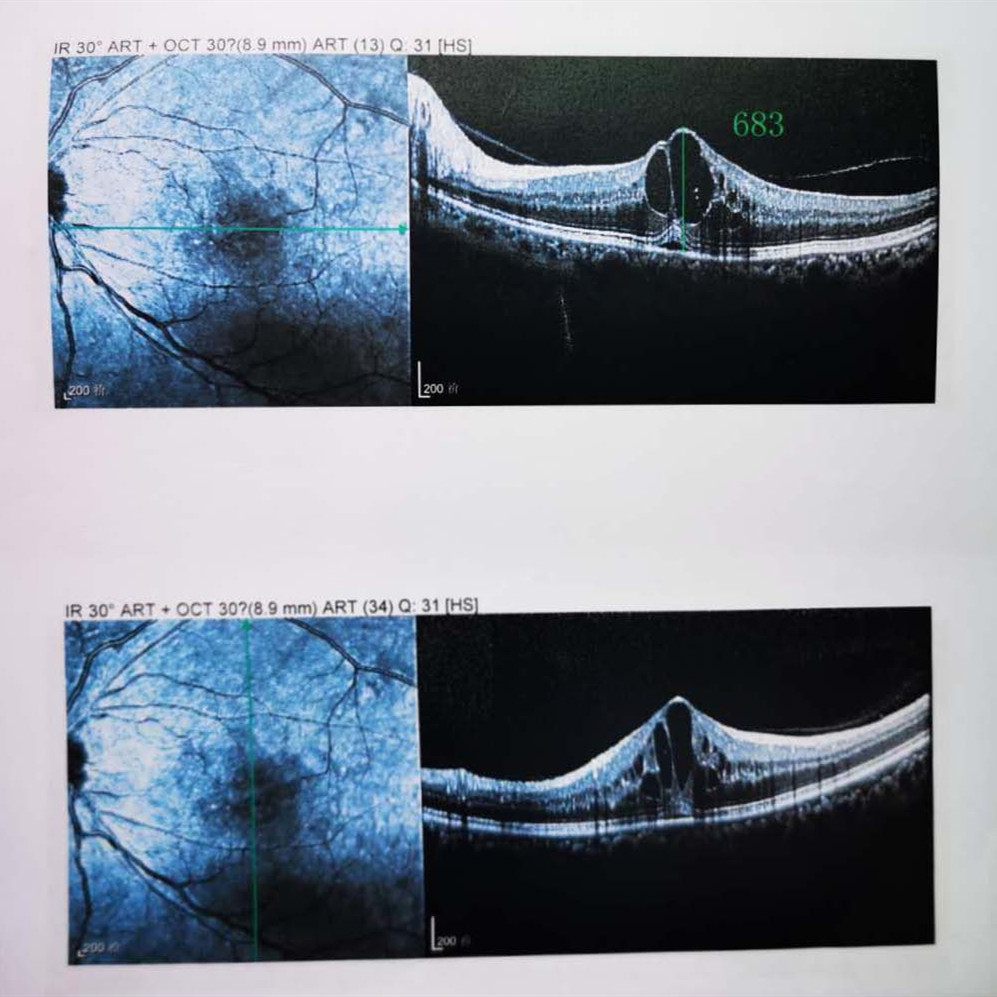

檢查結(jié)果顯示,武先生并沒有近視,右眼視力為1.0,但是左眼視力只有0.4,而且左眼視網(wǎng)膜各分支靜脈迂曲擴張,全網(wǎng)膜面見火焰狀出血,黃斑區(qū)高度水腫、滲出,黃斑中心凹厚度約683um。

OCT

(武先生初次就診眼底OCT檢查圖)

而正常的矯正視力是1.0,黃斑中心凹厚度在200um左右。

“你這黃斑都腫到正常人的三四倍大了!”廈門眼科中心吳國基院長醫(yī)生告訴武先生,“你這是左眼視網(wǎng)膜中央靜脈阻塞伴黃斑水腫,你左眼的視力下降、看東西變形,是因為你左眼視網(wǎng)膜的中央靜脈發(fā)生了阻塞、出血,導(dǎo)致眼底黃斑水腫了。”

那么,武先生的視力恢復(fù)情況如何呢?幸運的是,經(jīng)過兩次玻璃體腔注藥術(shù),武先生左眼的黃斑水腫得到明顯改善,視力已經(jīng)恢復(fù)到0.8。

(武先生出院時眼底OCT檢查圖)